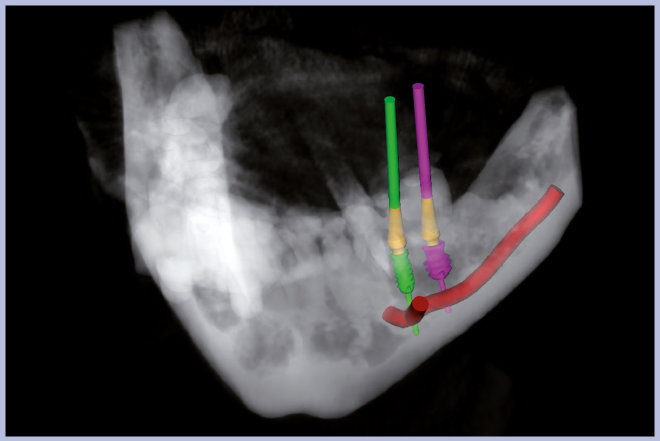

Per riabilitare la masticazione del terzo quadrante, con osso gravemente atrofico, si procede allo studio del caso con esame radiologico 3D e posizionamento virtuale di impianti Exacone® Leone. La prima valutazione è stata eseguita con il software dell’apparecchio radiografico Cone Beam presente in studio. Dopo aver verificato che la quantità di osso residuo fosse sufficiente all’inserimento di due impianti, seppur di dimensioni ridotte, in sede 3.5 e 3.6 senza l’ausilio di tecniche di rigenerazione ossea (Figg. 1-3), si richiede al laboratorio di confezionare una mascherina radiologica con ceratura diagnostica radiopaca e repere standardizzato a livello incisale come da protocollo Leone (Figg. 4, 5). Si verifica quindi clinicamente l’assenza di mobilità della mascherina dopo il posizionamento nel cavo orale del paziente (Figg. 6, 7). Si effettua una CBCT con la mascherina in posizione e l’esame viene inviato in formato DICOM all’azienda Leone assieme al modello master della paziente. L’azienda provvede quindi ad inviare agli Autori il software 3Diagnosys (software di progettazione) in licenza monopaziente con caricati i file DICOM ricevuti; il software viene quindi utilizzato per la progettazione definitiva del caso (Figg. 8-12).

- Figg. 8-12 – Pianificazione implantare con software 3Diagnosys Leone